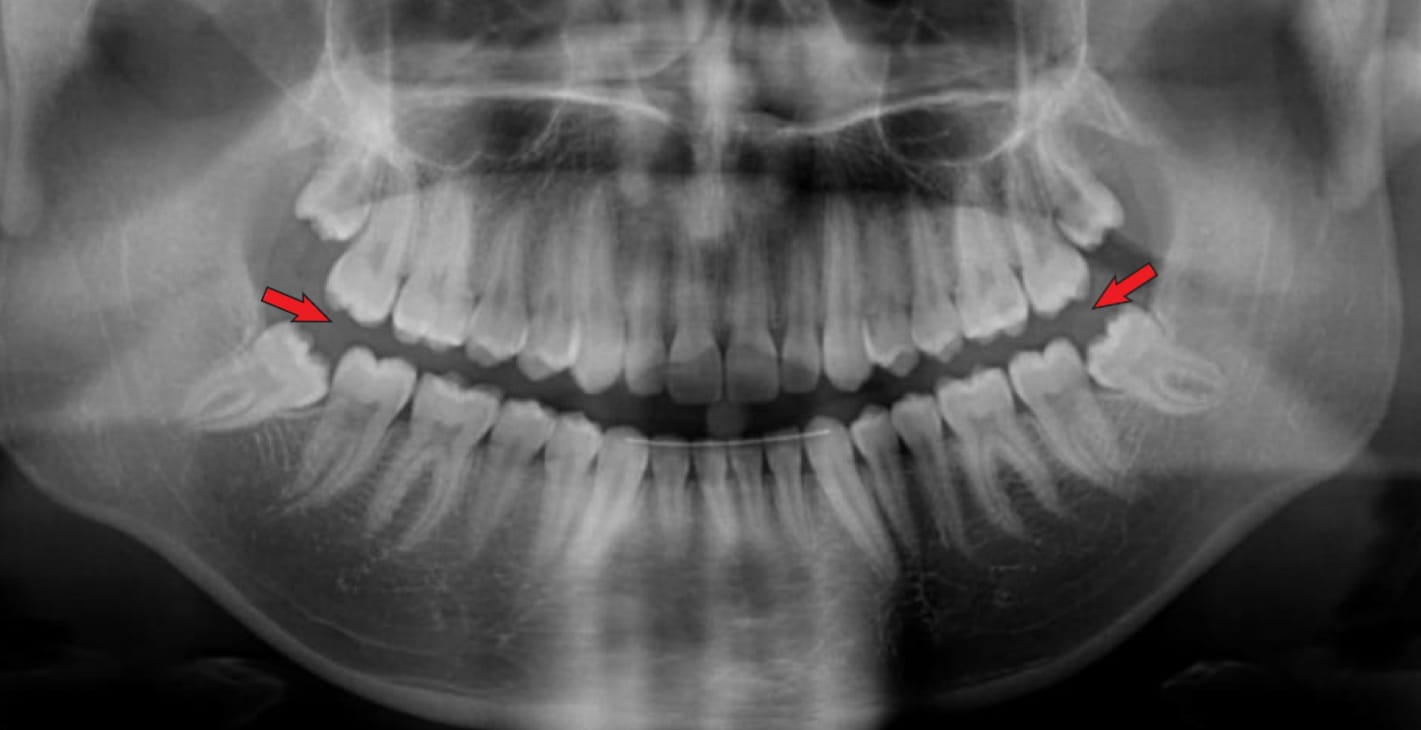

⚠️ Image fantôme

Une image fantôme consiste en un artefact radio-opaque qui apparaît dans une image panoramique et qui est causé par la double pénétration du faisceau de rayons X dans un objet. Cette image fantôme ressemble à l'image réelle, mais elle apparaît sur la face opposée du film, elle est plus grande et plus haute que l'image réelle, et elle est diffuse.

Solution : Demandez au patient de retirer tous les objets métalliques ou autres qui ne permettent pas aux rayons X de passer, tels que les lunettes, les boucles d'oreilles, piercings, colliers, prothèses amovibles, appareils orthodontiques amovibles, etc..

Image 1: Image fantôme